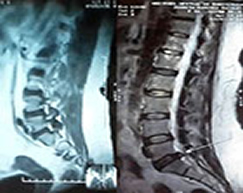

¡ Observe algunos ejemplos de los Casos Clínicos desde el 2007 al 2026 que han sido resueltos satisfactoriamente ! ... Hernia Discal de Columna Vertebral, Artrosis degenerativa, Osteoporosis y Osteopenia, Artritis Reumatoide, Gonartrosis de Rodillas, Ciática y Lumbalgia, entre otras ... ¡ Regenere, Fortalezca, Prevenga y Evite una Cirugía de su Columna Vertebral, Rodillas y Articulaciones ! ... ¡ Trátese Natural Sin Cirugía, en su Casa y a bajo Precio ! ... ¡ También Si lo desea, solicite Información y Precio para Ser un Distribuidor Independiente en su Ciudad, Estado y País !